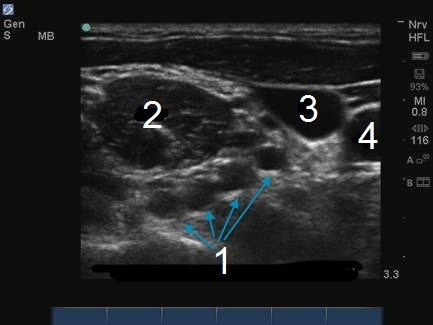

M-Turbo: Brachial Plexus Interscalene Level 4

1. Brachial Plexus - Interscalene Level

2. MSM

3. JV

4. CA